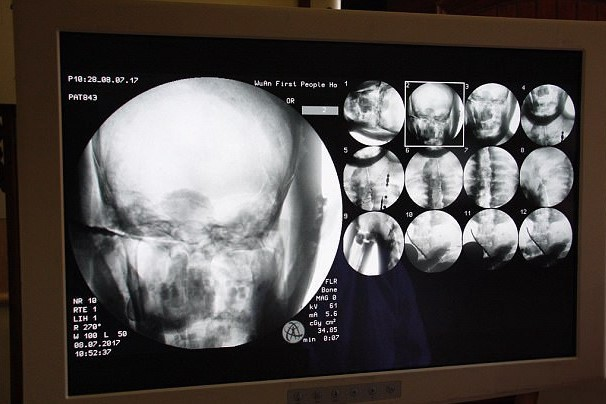

Компьютерная томография золотой статуи мастера Ци Сяня, изображающей труп внутри статуи (Источник: храм Дин Хуэй)

После компьютерной томографии исследователи, медики и другие монахи, которые были свидетелями этого события, остались абсолютно шокированы, узнав, что труп мастера Ци Сяня на самом деле был спрятан внутри золотой статуи и хорошо сохранялся более 1000 лет. Это было просто шокирующее открытие, изменившее наш взгляд на историю.